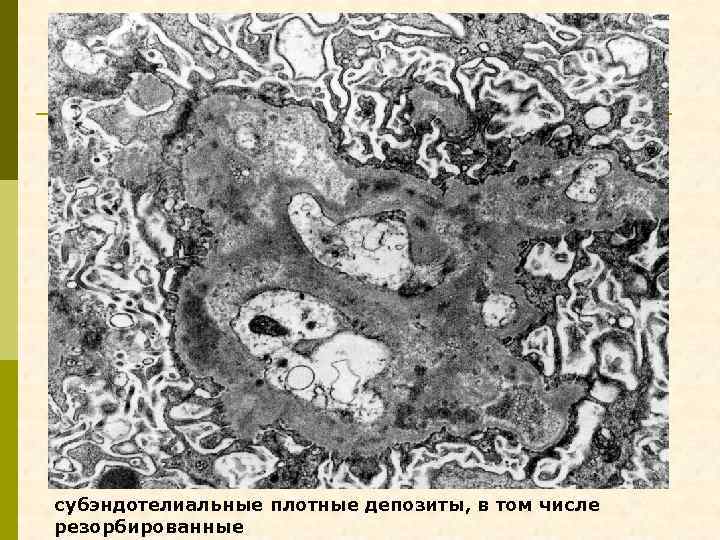

субэндотелиальные плотные депозиты, в том числе резорбированные